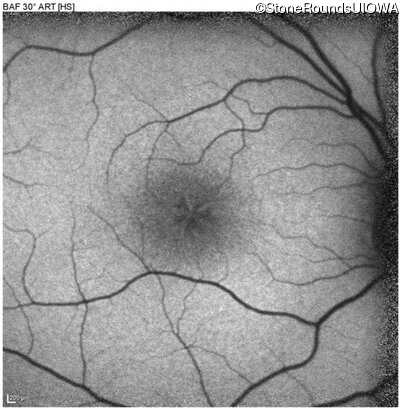

XL Retinoschisis (IIIB1)

XL Retinoschisis (IIIB1)

This 6 year old boy first experienced difficulty reading and seeing the blackboard at age 5.

| XL Retinoschisis | RS1 | Pro192His CCC>CAC | XL |